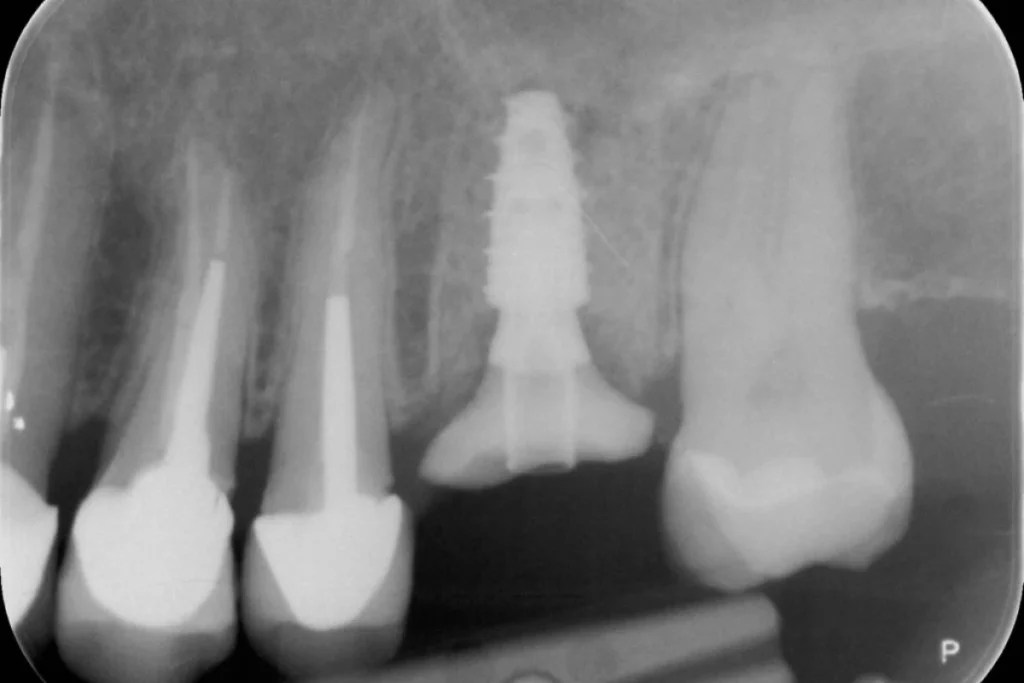

Nous vous présentons le cas de Mme B. 53 ans, qui consulte suite à des douleurs sur sa molaire supérieure gauche.

Après un examen clinique et radiographique, le verdict tombe… la dent n’est malheureusement plus conservable.

Après lui avoir exposé les différentes solutions, Madame B. souhaite remplacer sa dent par un implant. C’est la solution de choix pour retrouver une dent fixe sans avoir à abimer les dents de part et d’autre. L’analyse du scanner nous permet de proposer à Madame B. une extraction implantation immédiate. Il s’agit de réaliser en une seule et même séance l’extraction de la dent condamnée et la mise en place de l’implant dentaire.

Cela permet d’éviter une 2ème chirurgie à notre patiente et de raccourcir la durée du traitement de plusieurs mois. Un comblement osseux est réalisé le jour de l’intervention.

3 mois après la pose de l’implant, la patiente peut retrouver une dent fonctionnelle et esthétique.